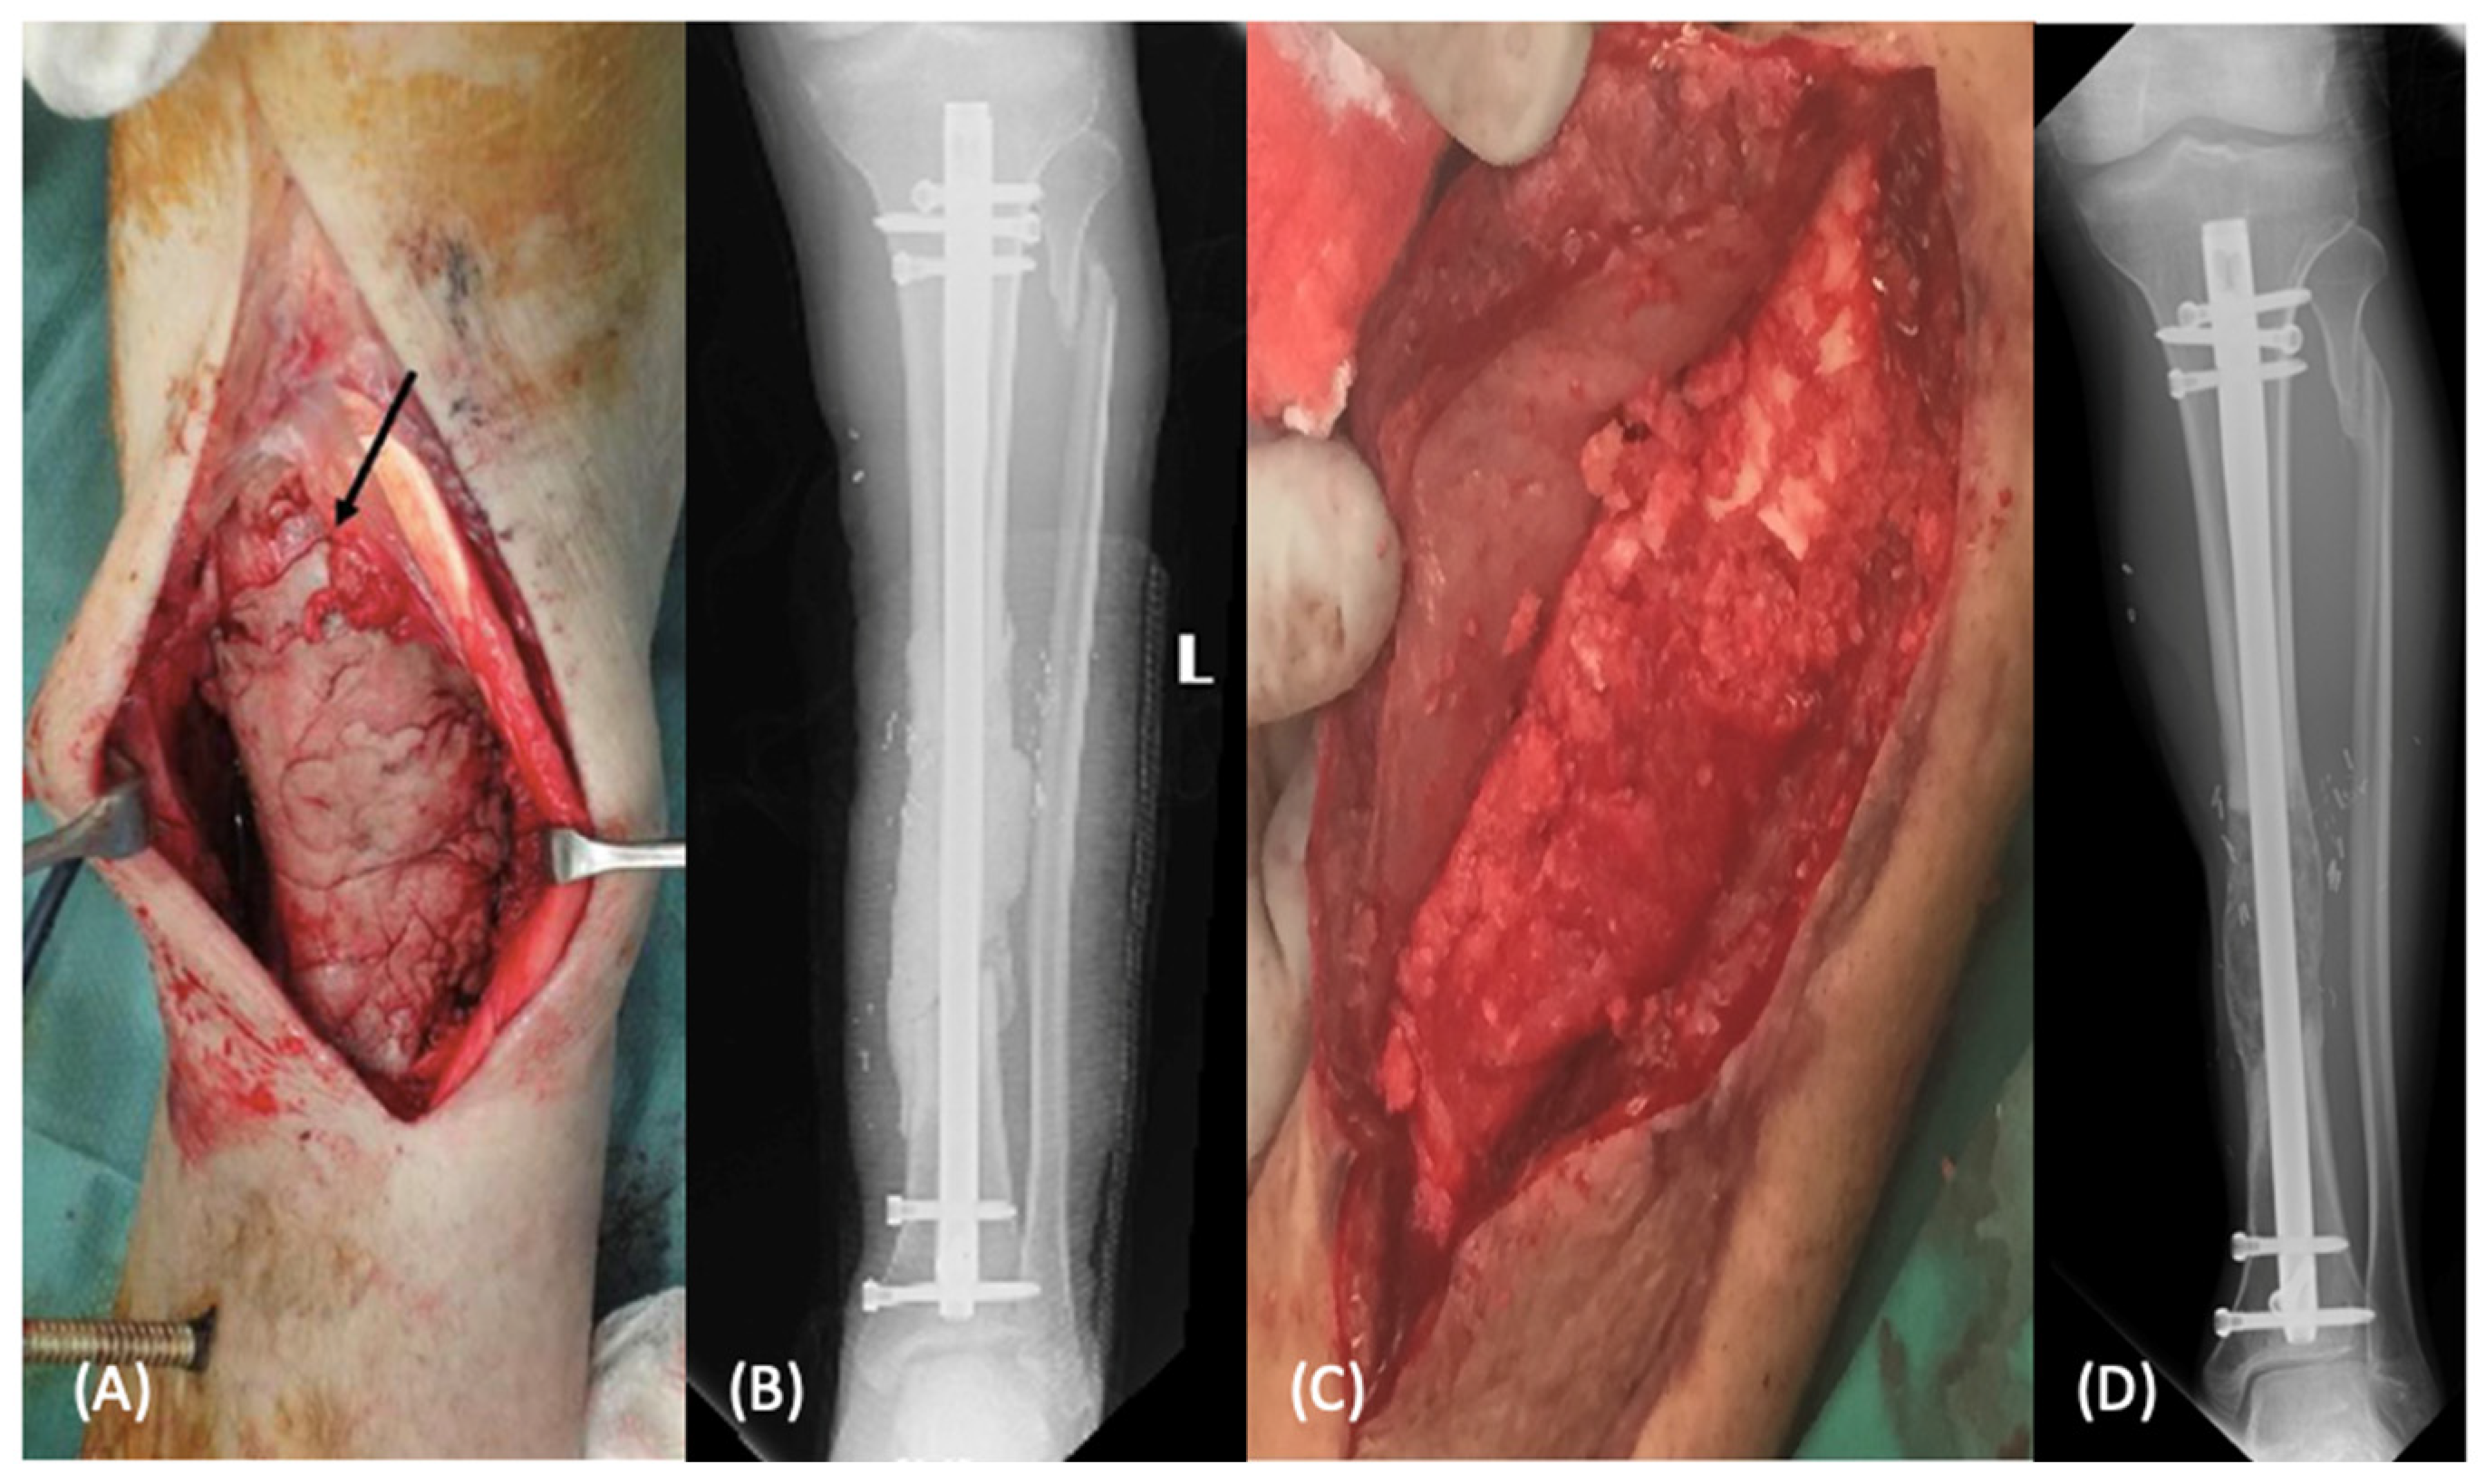

2.1.1. Induced Membrane Technique